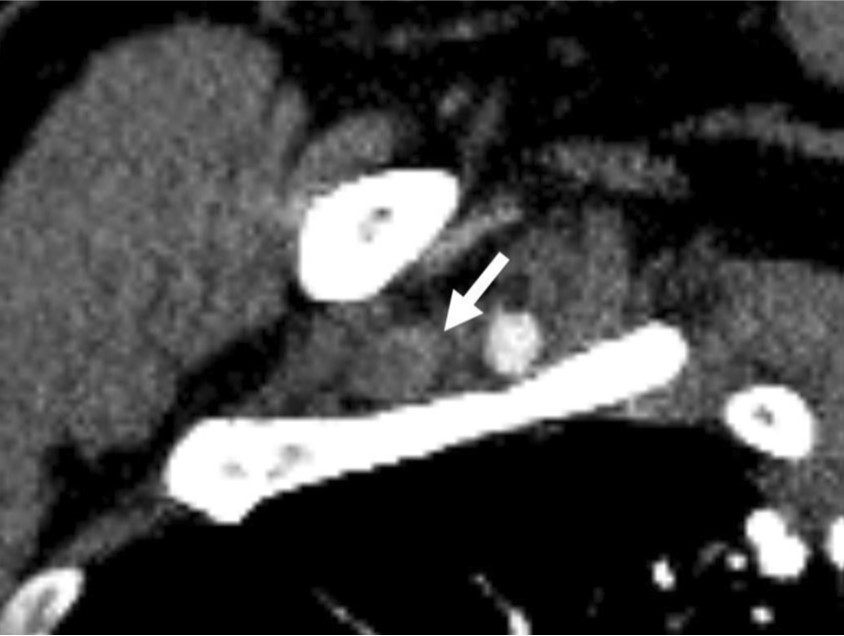

조영증강 CT에서 우측 쇄골하정 맥을 포함한 상지 심부정맥이 확장되어 있고 내부에는 혈전이 있었다(Fig. 1A-C). 우측 사각근간 삼각(interscalene triangle)에 의해 우측 쇄골하정맥이 명확하게 눌려진 소견은 없으며 우측늑쇄공간(costoclavicular space)도 좁아지거나 주변 구조물에 의해 눌려진 소견은 보이지 않아 반복적 인 작업에 의해 정맥이 눌린 노력혈전증( effort thrombosis)으로 생각하였다.

Fig. 1. A-C

Multiplan ar reconstructed images (A-C) shows contrast filling dtfecte (arrows) within right subclavian van.